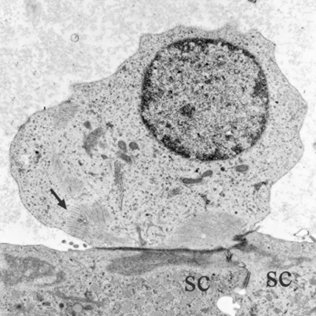

(6/14) We first discovered that the earliest steps in chronic damage are characterized by detachment of the #haircells from their afferent contacts in association with early loss of #vestibular function. And that both the histological and functional effects may be reversible.

(5/14) Before final extrusion, #vestibular #haircells must follow a complete program of morphological alteration. So we aimed at understanding the process.

(3/14) Standard experimental approaches had established that #haircells may degenerate by apoptosis. However, loss of #haircells may also proceed through a process of extrusion, in which the cell is ejected from the sensory epithelium